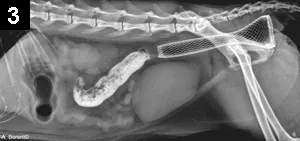

Figure 3. Lateral radiograph of a feline patient after a colorectal stent was placed for colonic stricture

In the author’s experience, colonic stents have been placed in veterinary patients primarily for tumors or strictures (after resection and anastomosis or postradiation therapy). In all cases, colonoscopy is performed to visualize and obtain a biopsy followed by fluoroscopy to guide stent placement over a guide wire (Figure 3); patency can be reestablished immediately. The stent has been seen to be incorporated into the colonic mucosa within 4 days.